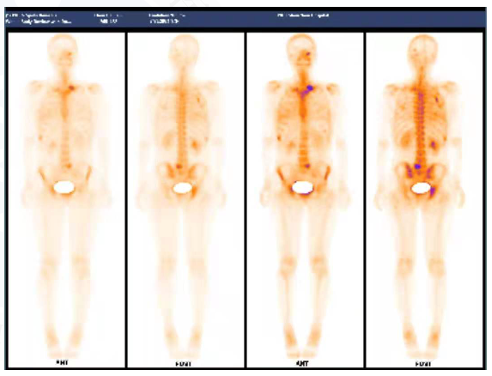

√ 2021.10全身骨ECT:新见枕骨、右侧肩胛骨、胸4椎体右半部、左侧第8前肋、右侧第8-9后肋、腰5椎体左半部、右侧髋臼、右侧坐骨局灶性团放射性分布异常浓集影。

图8骨ECT